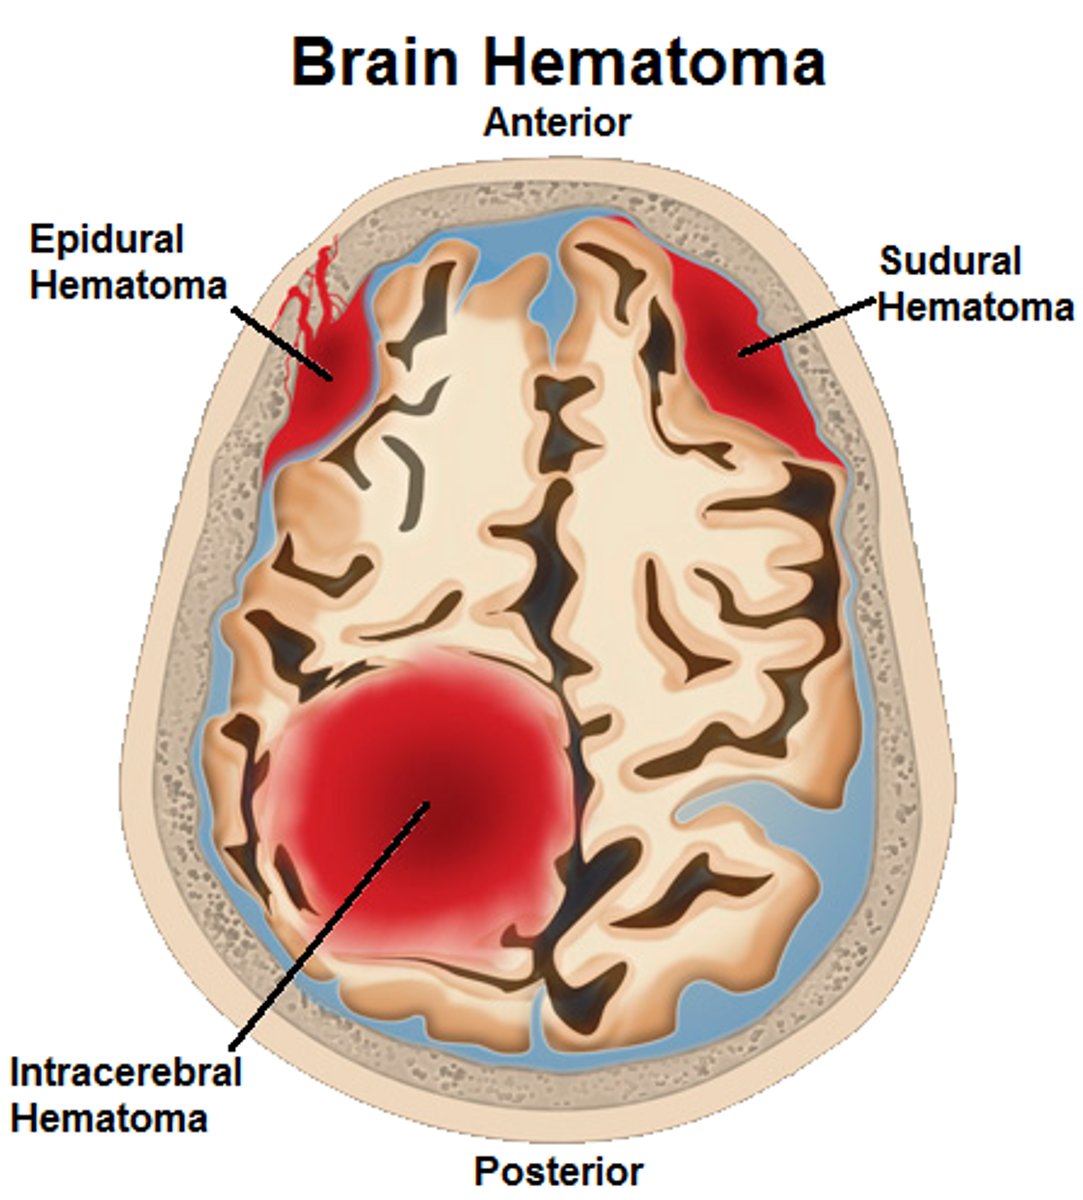

Types of Head Trauma

Concussion,

Contusion,

Subdural Hematoma,

Cerebral Edema

Concussion

Alteration in brain function following blow to the head

Contusion

Bruising in the brain and can cause permanent Neurological Damage

Subdural Hematoma

Blood vessels are broken in the brain

Cerebral Edema

Swelling on the brain